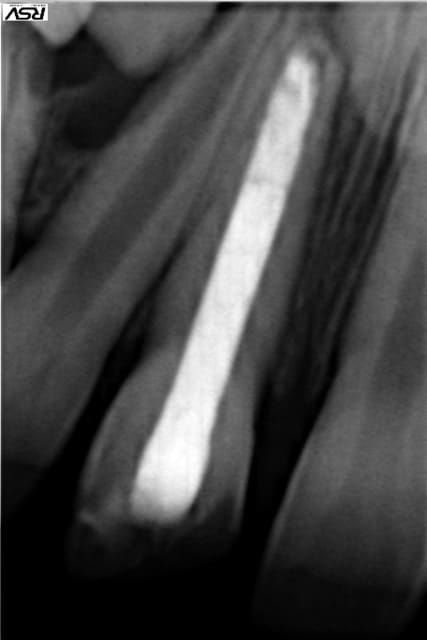

Patient, 20 ans, choc multiples sur les centrales étant gamin. Pano pour les 8.

Lésion sur 21, en bouche, légère dyschromie, test froid négatif, pas de douleur, retro, tu m'étonnes ... ! Les autres répondent correctement.

Concrètement, comment obturer convenablement ça ?

Bouchon de MTA : entre la galère pour appliquer ça correctement à l'apex et sans dépasser dans tous les sens, bof, de plus j'imagine que c'est utopique de vouloir obtenir ne serait-ce qu'un début de fermeture apicale.

Cônes de gutta moulés avec moultes Rx..., pourquoi pas, déjà fait, mais l'étanchéité ne semblerait pas optimale, ajouté au fait que le peu de ciment risque de fuser également.